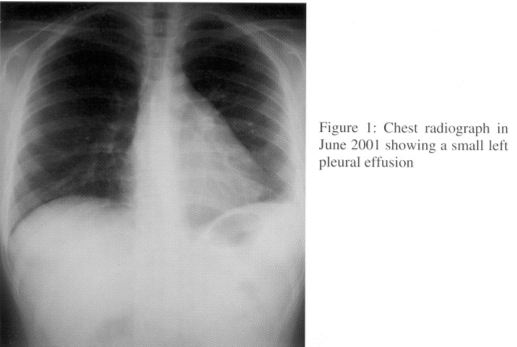

In June 2001, she presented to us with fever, multiple joint pain and left pleuritic chest pain for few weeks. Physical examination revealed left pleural rub. Chest radiography and ultrasound of thorax showed presence of mild left pleural effusion (Fig. I). Echocardiogram confirmed mild pericardial effusion, without evidence of any valvular dysfunction and pulmonary hypertension. Laboratory results revealed anaemia with positive direct anti-globulin test and increased SLE disease activity markers. The clinical picture was compatible with disease flare-up with serositis and haemolytic anaemia. She demonstrated both clinical improvement and radiological resolution of left pleural effusion after treatment with prednisolone 40 mg daily.